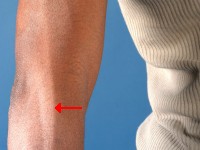

Causes lighter colored patches on the skin and nerve damage. This form of leprosy can affect sensation, primarily in the hand(s) and/or foot(s). You may injure yourself without realizing it. Excessive pressure and damage to the numb foot can cause wounds that are difficult to heal. If these wounds become severely infected, amputation may be necessary.

Sometimes the nerves to the muscles in the hands and/or feet are also affected, which can lead to paralysis. This leads to deformities such as foot drop or claw hand. Tuberculoid leprosy is not, or only slightly, contagious.